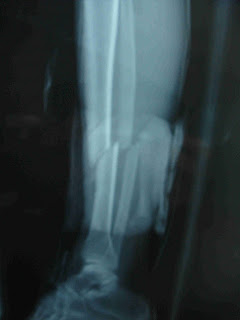

Non è stato scritto da nessuna parte ma sulla sabbia sono rimasti tibia e perone... assieme alla valigia... :lol:

...contento lui...:(

mi sarebbe piaciuto vedere le immagini successive

http://4.bp.blogspot.com/_HcpX_T7hAR...ura+perone.JPG

:confused:

....minkiaaaaa :mad::mad::mad:

che per tenerla su s`é rotto una gamba!!

Povera gamba!!! Chissa' se riuscira' a non zoppicare in futuro:confused: